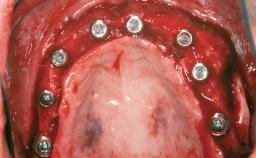

A 46-year-old woman was referred for treatment whose main complaints were mobility of her fixed partial dentures (right maxilla and left mandible) and periodontal bleeding during function. She also reported having taken systemic antibiotics to treat recurrent swelling in the area of the upper left molars. The patient had not seen a dentist for at least 2 years. She did not smoke and had no history of major systemic disease other than two minor orthopedic procedures some years back. The first-visit examination revealed poor plaque control, tooth mobility, periodontal disease, and a residual dentition widely associated with deep periodontal pockets.